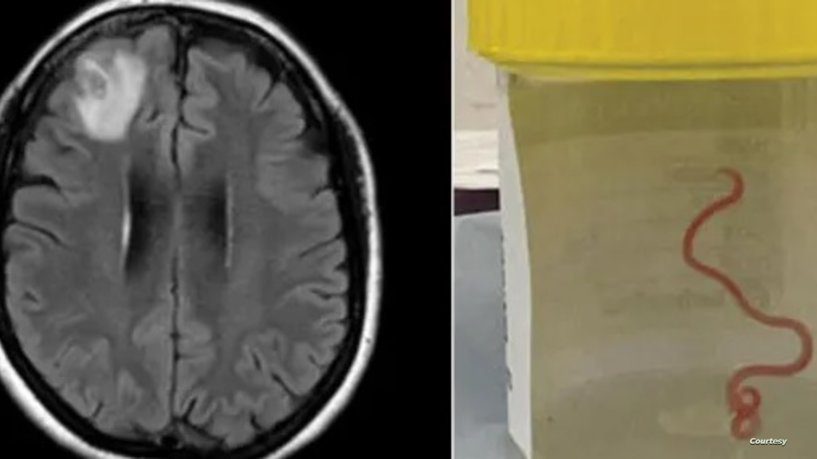

شكت من آلام مستمرة.. أول حالة بالعالم لـ\"دودة ثعابين\" بدماغ مريضة

اكتشف أطباء في مستشفى كانبيرا في أستراليا دودة حية كانت تعيش في دماغ امرأة، وفق صحيفة الغارديان.وسحبت جراحة الأعصاب، الد...